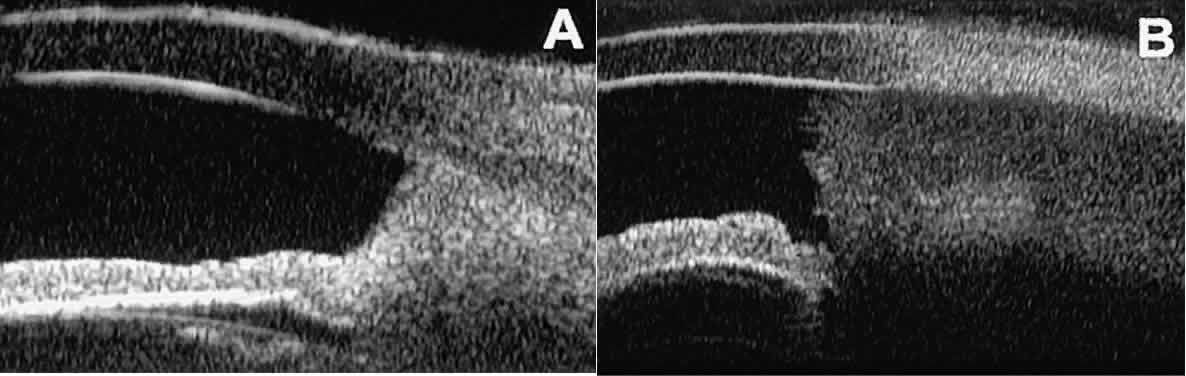

After any type of glaucoma filtering surgery,10 UBM can be used to detect and evaluate the extent of postoperative complications such as ciliochoroidal effusion and cyclodialysis.3,4 In ciliochoroidal effusion (Fig. 13A), UBM shows the ciliary body to be edematous and separated from the sclera by a sonolucent collection of supraciliary fluid. Many ciliochoroidal effusions that are too limited in extent to be detectable by indirect ophthalmoscopy and slit lamp biomicroscopy can be imaged by UBM. In cyclodialysis (see Fig. 13B), UBM shows a well-defined separation between the uveal tissue and the sclera in the region of the scleral spur. The width of the cleft is usually assessed best by means of limbus-concentric images through the region of interest.

Fig. 13. Complications of intraocular surgery. A. Postoperative ciliochoroidal effusion appears as slitlike spaces filled with serous fluid posterior to scleral spur. B. Postoperative cyclodialysis appears as complete separation of iris and ciliary body from sclera in region of scleral spur.